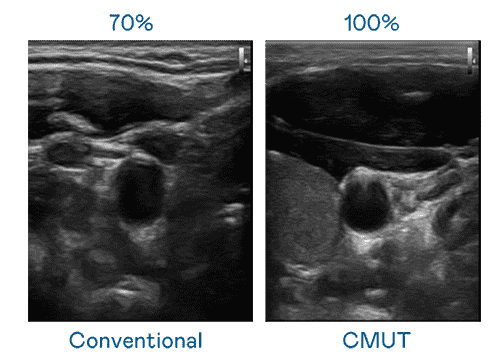

CMUT 技术是一种用电容式微机电元件来产生超音波讯号的技术。。与传统 PZT 压电式技术相比,,,CMUT 频宽增加 30%,,,,更宽频的超音波讯号让影像解析度大幅提升,,,,是实现高影像品质医疗超音波扫描、、促进精准医疗发展的关键技术。。

超音波影像的解析度高低,,,,首先取决于探头能发出的讯号频宽。。。彩霸王 CMUT 可提供高清晰的超音波讯号,,,,提供高频宽、、、高灵敏度、、、影像纹理细节更高的超音波影像,,协助医护人员缩短影像判读时间及利用精准的医疗影像进行诊断。。。